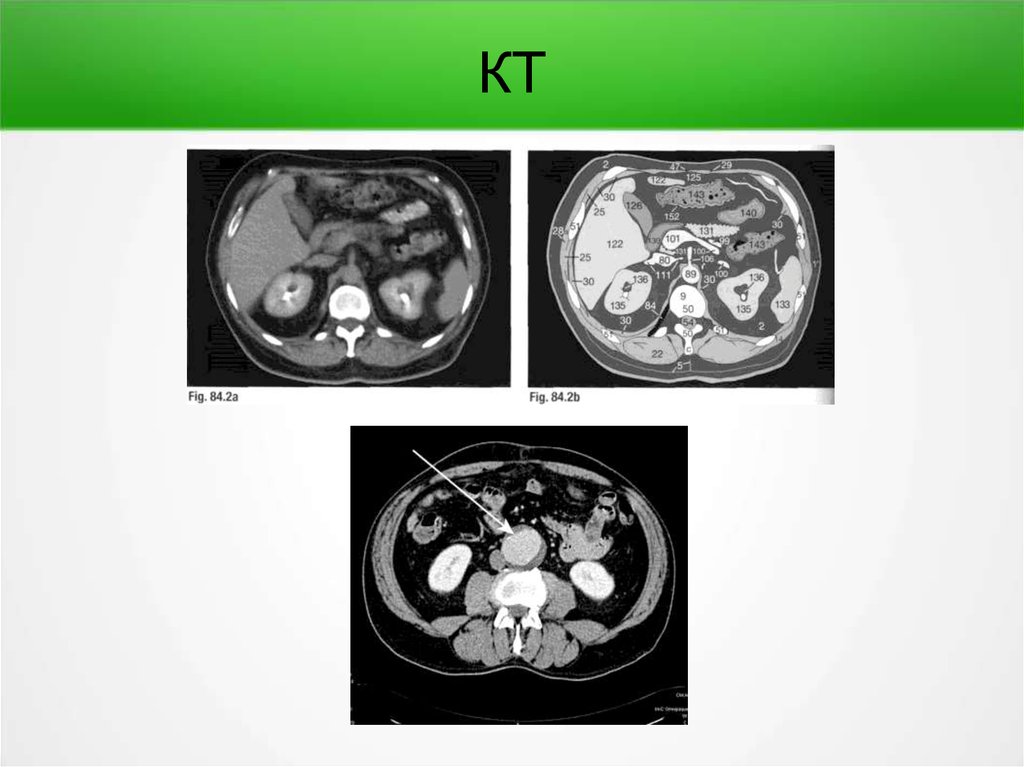

КТ